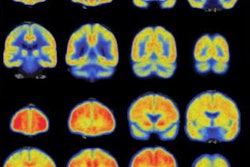

People at risk for Alzheimer's disease who do more moderate-intensity physical activity -- but not light-intensity activity -- are more likely to have healthy patterns of glucose metabolism in their brain. Image courtesy of the University of Wisconsin-Madison.Senior author Ozioma Okonkwo, PhD, and colleagues determined that moderate physical activity, which is equivalent to a brisk walk, was associated with greater levels of glucose metabolism in all brain regions viewed on FDG-PET. In addition, subjects who spent at least 68 minutes per day engaged in moderate physical activity showed better glucose metabolism profiles than those who spent less time.